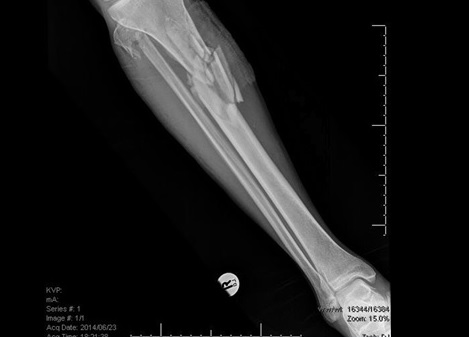

Fig6. - Midshaft tibia fracture.

Fig6. - Treated with an intramedullary nail